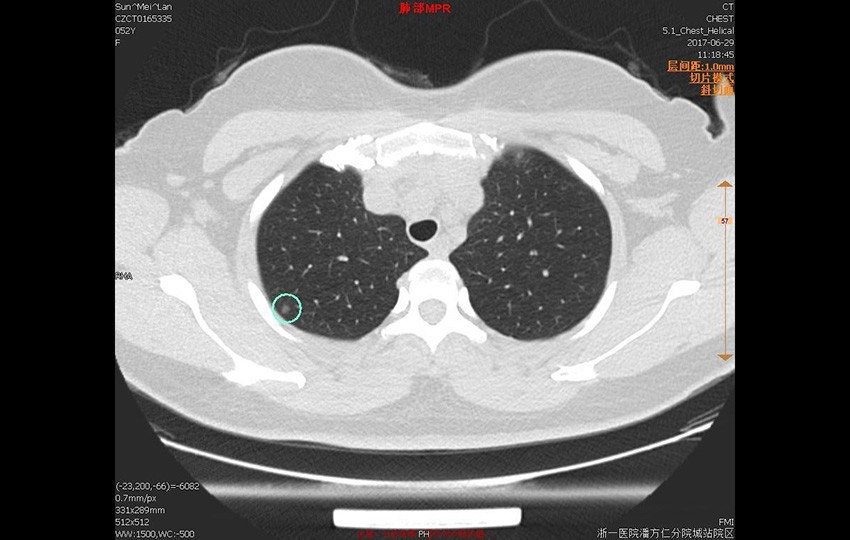

Пример 1-1<br>Анализ легочных узелков

Анализ легочных узелков